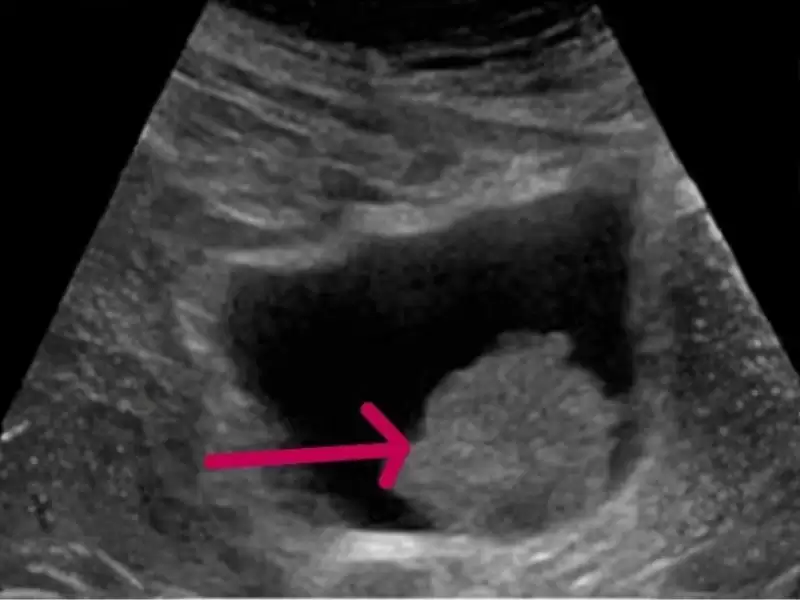

Prostat kanseri şüphesinde kullanılan füzyon biyopsisi; hedefli örnekleme sağlayan bir yöntemdir ve özellikle şüpheli MR bulgularında tanı d...

Prostat kanseri şüphesinde uygulanan füzyon biyopsisi, MR ile belirlenen şüpheli alanlardan hedefli doku örneği alınmasını sağlayan bir tanı...